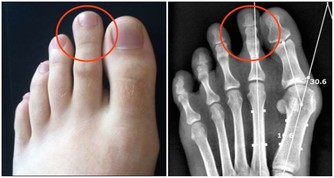

血壓處於一天中最低值,糖尿病病人易出現低血糖,心腦血管患者易發生心梗等。